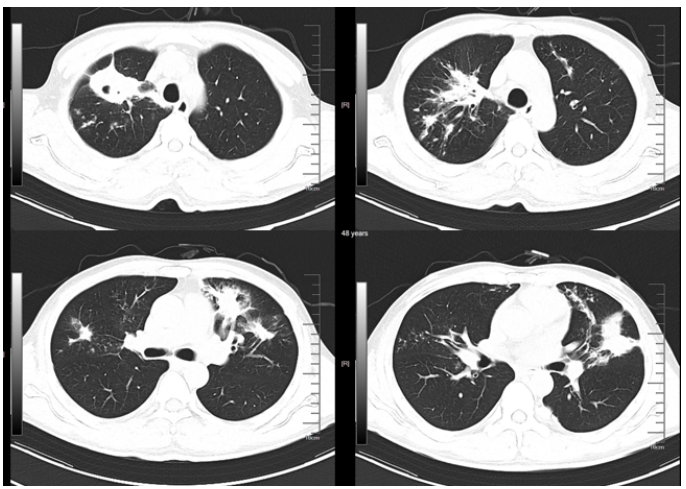

新冠病区诊治过程:鼻导管吸氧;阿兹夫定5 mg qd抗病毒、莫西沙星0.4 g qd抗感染,丙球10 g qd,地塞米松6 mg×2 d,之后予甲泼尼龙40 mg bid抗炎,低分子肝素钠5000单位ih q12h抗凝等治疗。2023年1月10日胸闷气急症状加重。血气分析(FiO2 41.0%):pH 7.39,PaO2 35.6 mmHg,PaCO2 34 mmHg,氧合指数87 mmHg。胸部CT(2023年1月10日,我院):双肺斑片影,符合病毒性肺炎,且较2023年1月6日明显加重(图1);双肾萎缩;双肾结石。

图1  患者胸部CT

1月17日复查胸部CT:双肺磨玻璃影较前有所吸收(图2)

图2  复查胸部CT(2023-01-17)

转入我科后患者体温热峰似乎有所下降,但仍有低热。1月27日复查胸部CT可见新冠肺炎病灶吸收、空洞形成,其中见小结节。支持真菌感染(图3)

图3  复查胸部CT(2023-01-27)